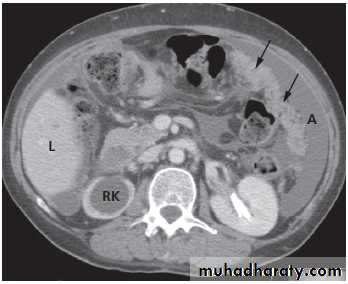

A dermoid cyst can usually be confidently diagnosed because of the fat within it, and it may contain various calcified components, of which teeth are the commonest.

These ovarian tumours are predominantly benign and can usually be recognized on ultrasound but are also readily diagnosed on CT or MRI and sometimes on plain radiographs .